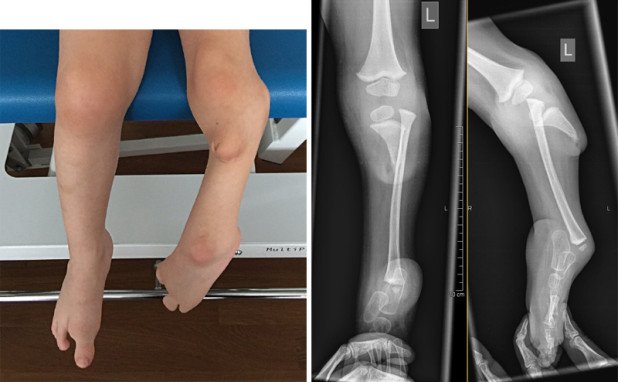

Schwere angeborene Fehlbildung des Beines – Rekonstruktion statt Amputation

Eine derart schwere Fehlbildung wie diese Tibiaaplasie (fehlende Anlage des Schienbeines) ist hierzulande nicht selten ein Grund für eine Amputation der Extremität. Neue operativ-technische Verfahren erlauben aber eine «Rettung» der Extremität.

In diesem Fall fehlt das Schienbein bis auf einen kleineren Anteil am Kniegelenk. Das Wadenbein ist jedoch weitestgehend normal entwickelt. Problematisch war bei diesem Mädchen aber auch der um 90 Grad fehlgestellte Fuss. Nach der Entscheidung für eine Rekonstruktion der Extremität mit dem Kind und den Eltern haben wir zunächst einen äusseren Fixateur (Taylor Spatial Frame) implantiert. Anschliessend haben wir über drei Monate die Weichteile distrahiert (gestreckt) und damit gleichzeitig computerassistiert den Fuss in eine korrekte Stellung gebracht.